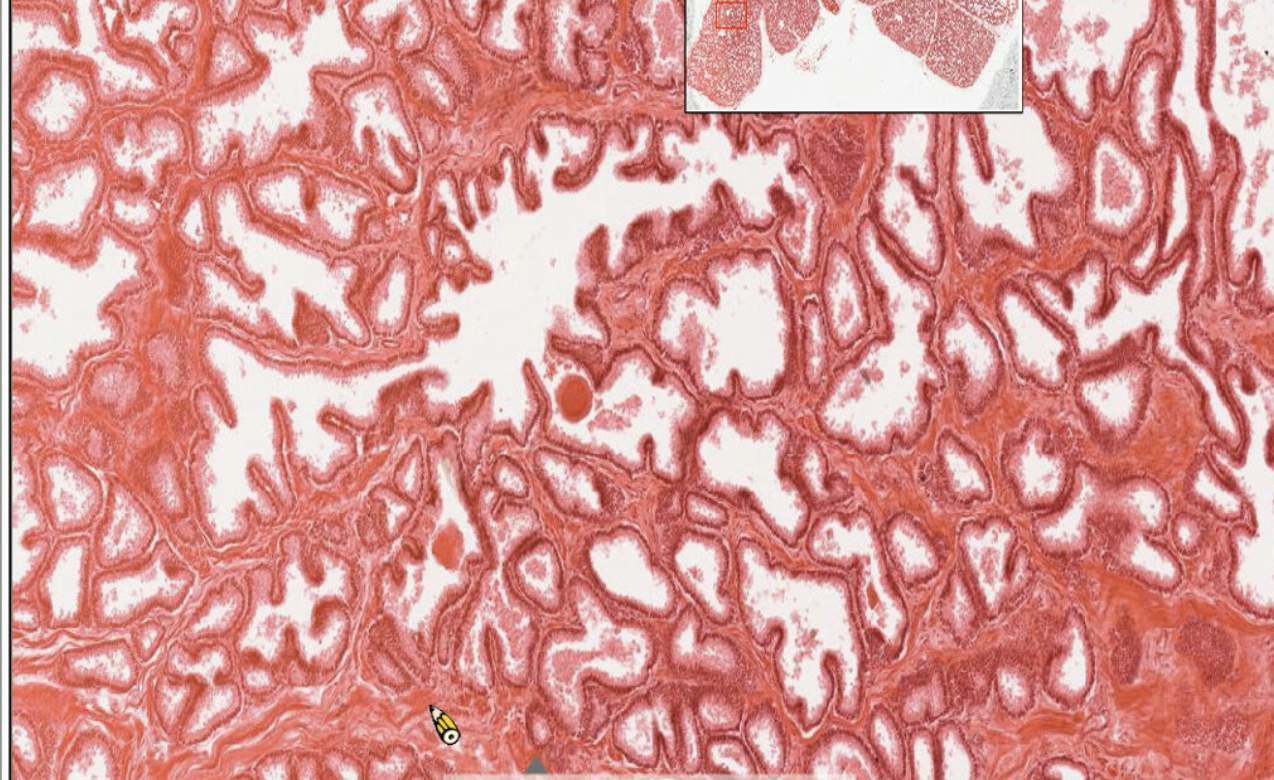

消化系統

Lab

Seminal Vesicle

Prostate Gland